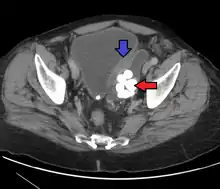

| Transitional cell carcinoma | |

| Other names | Urothelial carcinoma |

![]() | |

| Histopathology of transitional carcinoma of the urinary bladder. Transurethral biopsy. Hematoxylin and eosin stain. | |

Transitional cell carcinoma, also called urothelial carcinoma, is a type of cancer that typically occurs in the urinary system. It is the most common type of bladder cancer and cancer of the ureter, urethra, and urachus. Symptoms of urothelial carcinoma in the bladder include hematuria (blood in the urine). Diagnosis includes urine analysis and imaging of the urinary tract (cystoscopy). Transitional cell carcinomas arise from the transitional epithelium, a tissue lining the inner surface of these hollow organs.[1] When the term "urothelial" is used, it specifically refers to a carcinoma of the urothelium, meaning a transitional cell carcinomas of the urinary system.